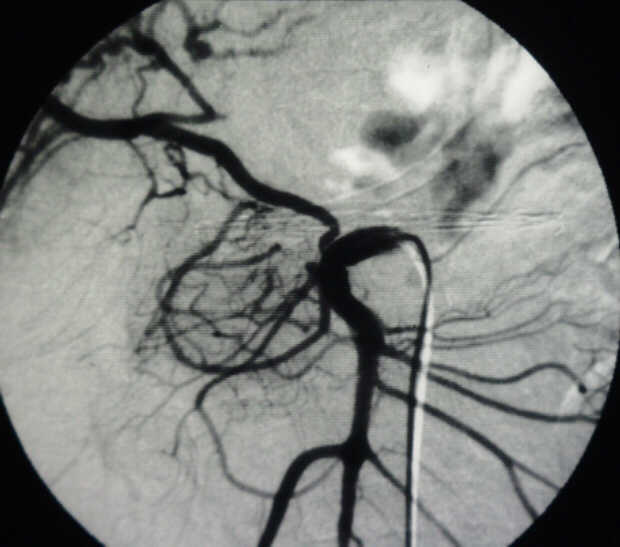

Diagnosis: Angiography

Giuseppe Morelli Coppola, Raffaella Niola, Franco Maglione

Unità Operativa di Radiologia Vascolare ed Interventistica, Azienda Ospedaliera "A. Cardarelli". Napoli, Italy